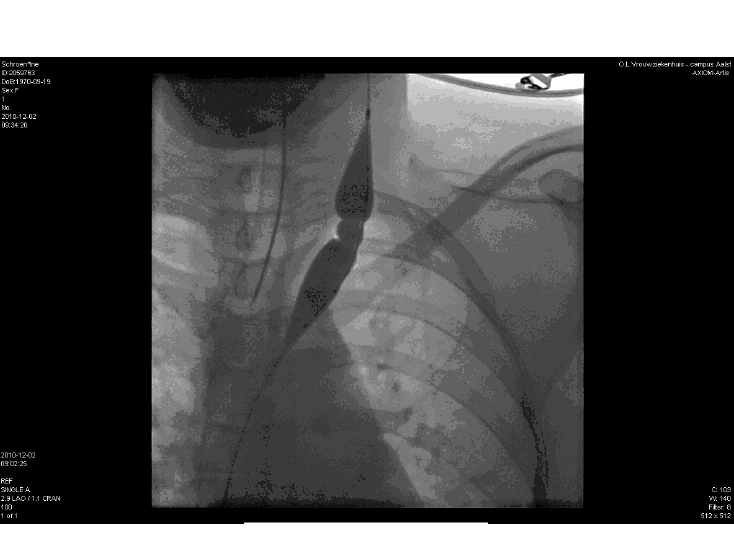

Opmerkingen bij bestand: Linker Jugularis, hoge stenose

viewer.png